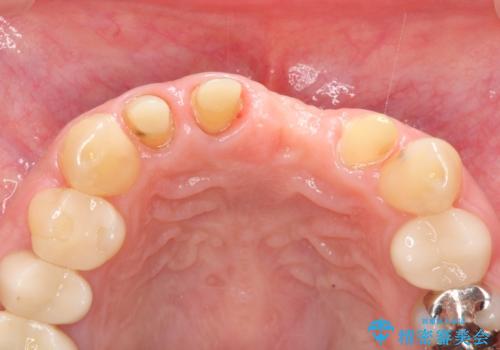

左側の前歯には他院で埋入されたポジションの悪いインプラント補綴により歯冠長の長いクラウンが装着されており、感染による排膿も認められこのまま審美性を改善するのは難しい状態です。

不良インプラントを除去し最終的にブリッジによる補綴で審美性の改善を行うこと、その準備として骨の造成・歯肉の移植による歯の欠損部顎堤のボリュームを維持・増大を計画します。

感染したインプラントからは排膿が間欠的に認められ、掻爬・除去が検討されうるような状況でした。

より審美的な改善を強く求められたため、インプラントを除去し可及的に欠損部顎堤を増大したのちブリッジによる審美改善を行いました。